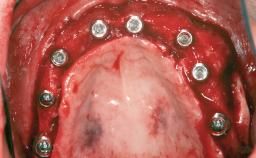

A 20-year-old woman was referred for implant therapy in 2004. Her medical history revealed no significant findings, and neither did she smoke nor take any medications. An extraoral examination revealed no abnormalities of the skin, hair or nails. The intraoral examination revealed only 11 permanent teeth clinically. These were normal in shape, size, and color. In addition, eight retained deciduous teeth (53, 62, 63, 71, 72, 73, 81, 82) were present. No abnormalities were detected during the general examination. The family history revealed that the patient’s father and two sisters were on record with similar conditions. The clinical examination revealed a thick gingival biotype. No recession of the attached gingiva was noted, but the retained deciduous teeth were mobile and unsightly. As a syndrome had not been diagnosed, the case was categorized as non-syndromic oligodontia.

# of Implants 12

Type of Implants One-Piece|Reduced-Diameter